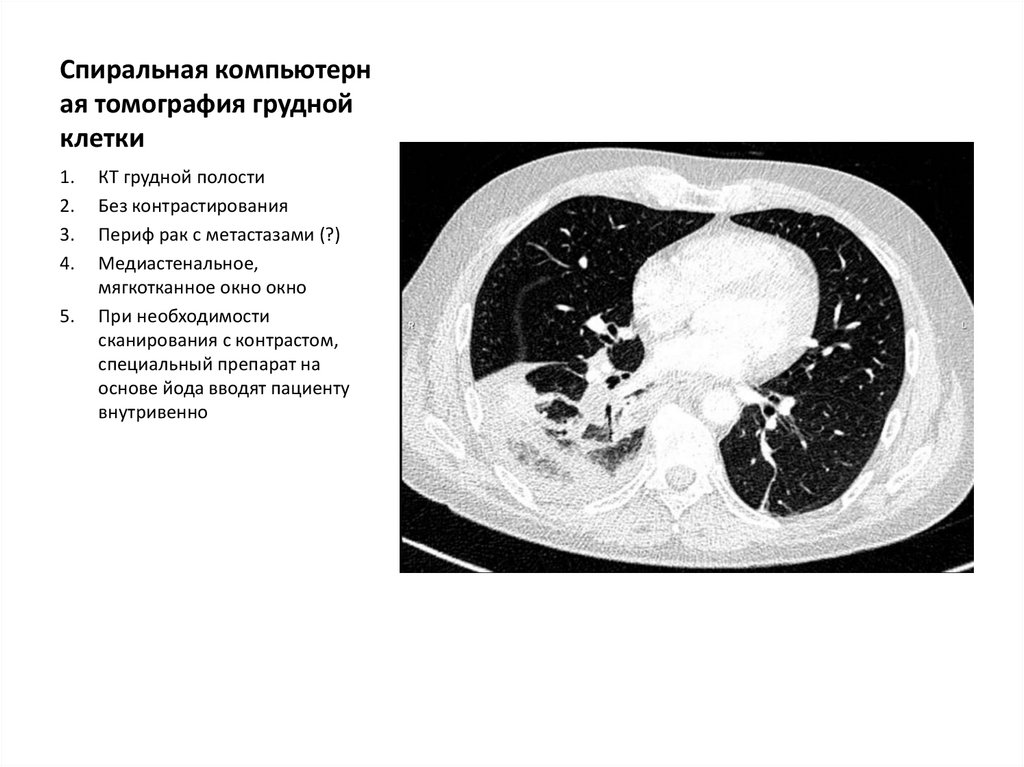

Спиральная компьютерн

ая томография грудной

клетки

КТ грудной полости

Без контрастирования

Периф рак с метастазами (?)

Медиастенальное,

мягкотканное окно окно

При необходимости

сканирования с контрастом,

специальный препарат на

основе йода вводят пациенту

внутривенно